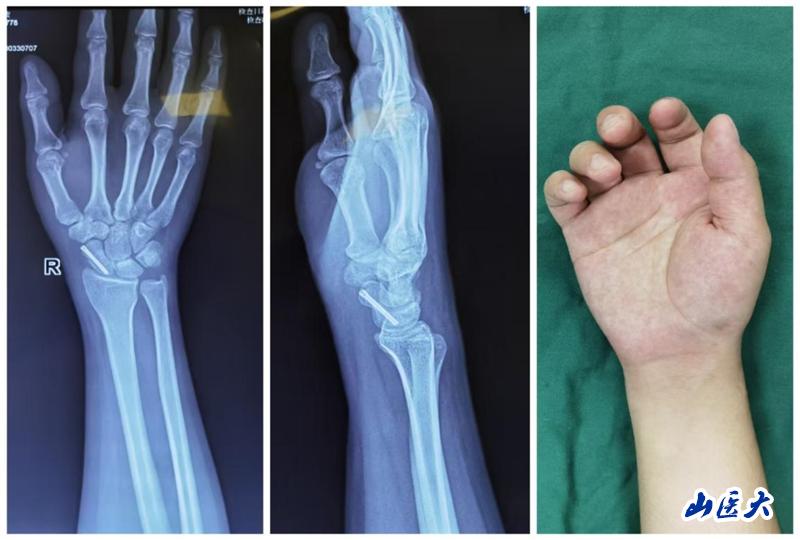

患者是一位年僅21歲的男性患者,他在上學途中不慎騎自行車摔倒,導致右腕部劇烈疼痛、腫脹并活動受限。經過X線片檢查,確診為右側舟骨骨折。患者曾在重慶某三甲醫院接受石膏固定術,但為尋求更專業的治療,選擇到我校第二醫院西院區就診。

考慮到患者年輕且希望盡快恢復,王建國團隊在詳細討論并與患者及家屬充分溝通后,決定采用微創經皮螺釘復位內固定術這一先進治療方法。手術過程中,醫療團隊借助C臂機透視引導進行精準定位,僅通過一個微小的2mm切口,就成功置入螺釘完成了內固定。術后,患者疼痛明顯緩解,復查X線片顯示螺釘位置良好,腕關節功能活動也恢復得相當不錯。